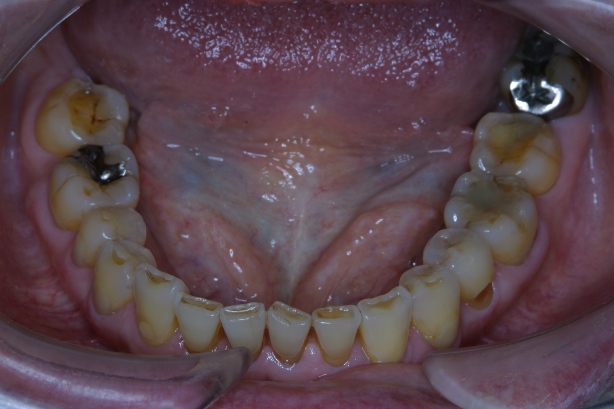

「8020運動」 表彰に出て頂いた方々のお口を拝見